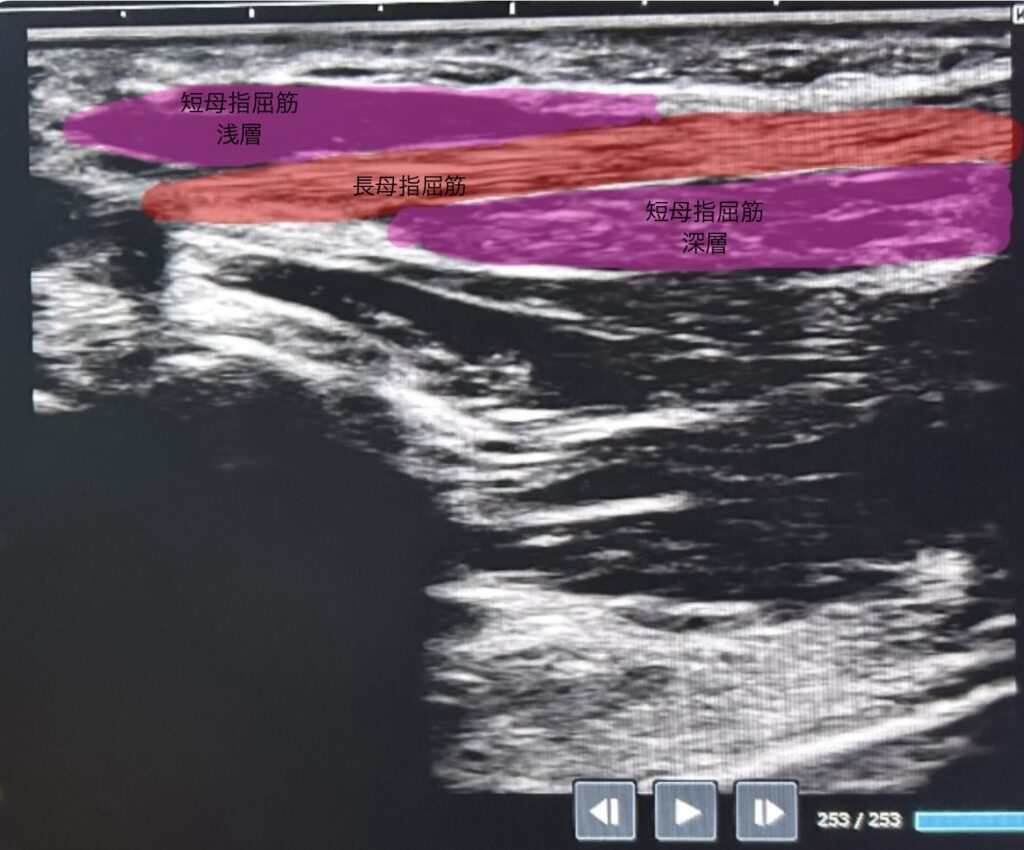

②少し内側へ移動

長母指屈筋に対して長軸でみると、、、

長母指屈筋:末節骨の屈曲

短母指屈筋:基節骨の屈曲

浅層(正中神経支配)

深層(尺骨神経支配)となる。